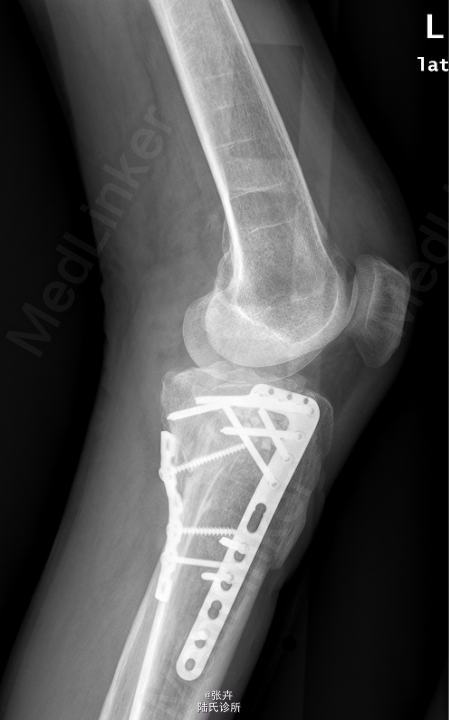

初步诊断:左胫骨平台骨折。行左胫骨平台骨折切复内固定+人工骨植骨术。

注意术后关节功能锻炼。